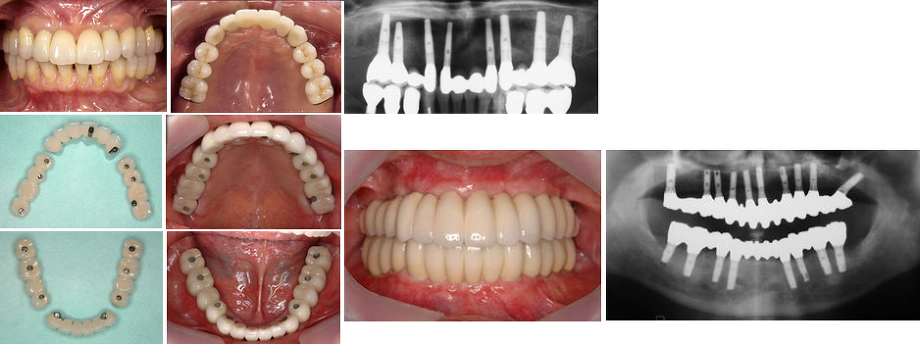

5.極度の骨欠損がある7歯欠損症例

(症例 6、歯槽骨延長術と自家骨移植)

極度の骨欠損があったが、歯槽骨延長術と下顎枝部からの自家骨移植にて審美的インプラント治療を行いました。

歯槽骨延長術では他の部位からの骨採取(骨移植の場合は必ず他の部位から骨採取が必要です)をする必要がなく、その部位の骨に切れ目を入れ、骨延長器を使って1日0.2-0.5mmずつ骨を伸ばしていく方法です。必要な量だけ骨を伸ばすことが可能であり、同時に歯茎も伸ばせる利点もあります。

非常に特殊な術式なので、行える医療機関はほとんどないのが現状です。当院では、40症例の経験があり、インプラント関係で最も権威のある 学会雑誌に掲載されました(Antero-inferior Distraction of the Atrophic Subtotal Maxillary Alveolus for Implant Placement: A Case Report.International Journal of Oral and Maxillofacial Implants (JOMI).2002; 17(3): 416-423. )

無歯顎(歯が全部ない状態で、上顎だけ、下顎だけ、あるいは上顎・下顎の両方)の患者さんでは、インプラントを埋め込んだ日に仮の歯を付けることができます。 この治療法は即時荷重(immediate loading)と呼ばれ、インプラント治療の中で最も高度な技術を要する治療であり、当院は1997年から行っている。。この成果は、ブローネマルクインプラントの発祥地であるスウェーデンのイエテボリで2000年7月に開催されたInternational TeamDay of Nobel Biocare(この会議には世界的な著名人をはじめ約2000名のインプラント関係者が世界中から参加されました)にて、招待講演(Immediate loading of Complete Arches Prostheses with Implant support from Posterior mandiblae and maxillae)として発表した。この内容はインプラント関係では最も権威のある International Journal of Oral and Maxillofacial Implants (JOMI) という学会雑誌に掲載された( Immediate Loading of Brånemark System Implants Following Placement in Edentulous Patients: A Clinical Report . 2000;15(6):824-830 )。

無歯顎即時荷重において “All-on-4” がトピックスとなっており、治療オプションの1つとして利用価値があるかもしれないが、十分な知識と術式の習得をした上でないとトラブルが生じる可能性が高い。また、①日本人の上顎では適用できない症例も多い、②補綴の自由度がない、③第2大臼歯間の咬合再建ができない、➃最遠心インプラントの角度付アバットメントにおけるアバットメントスクリューの緩みによるトラブル、➄長期のデータがない、などが問題点と考えられ、当院では応用していない。補綴の自由度に関しては、 インプラント4本での“All-on-4” は ワンピース(一続きの)の補綴物しか作製できないが、 8本ないしは10本のインプラントを埋入すれば、前歯部、両側臼歯部の 3つに分割した補綴物にすることが可能である。

無歯顎即時荷重において “All-on-4” がトピックスとなっており、治療オプションの1つとして利用価値があるかもしれないが、十分な知識と術式の習得をした上でないとトラブルが生じる可能性が高い。また、①日本人の上顎では適用できない症例も多い、②補綴の自由度がない、③第2大臼歯間の咬合再建ができない、➃最遠心インプラントの角度付アバットメントにおけるアバットメントスクリューの緩みによるトラブル、➄長期のデータがない、などが問題点と考えられ、当院では応用していない。補綴の自由度に関しては、 インプラント4本での“All-on-4” は ワンピース(一続きの)の補綴物しか作製できないが、 8本ないしは10本のインプラントを埋入すれば、前歯部、両側臼歯部の 3つに分割した補綴物にすることが可能である。

以上の観点から当院では、患者さんの信頼をなくさないための予知性が高い、そして機能的かつ審美的に優れた即時荷重を300例以上行い、良好な結果を得ている。

4年前からノーベル・バイオケア社のNobelGuideによるコンピュータ・ガイディッド・サージェリー(Computer-guided surgey: コンピュータにてインプラント治療計画を立て、その通りに手術が可能になる手術法)にて低侵襲でかつ短時間の治療が可能となった。

しかし、上顎では上顎洞(上顎骨にある空洞で副鼻腔の一つ)との関係で骨量が少ない症例が多く、グラフトレス(graftless: 骨造成をしないという意味)では対応できず、最低限度のグラフト(graft: 骨造成をするという意味)を行う必要があり、当院ではそれを行うことにより、上顎無歯顎症例の96%に即時荷重を可能にしている。